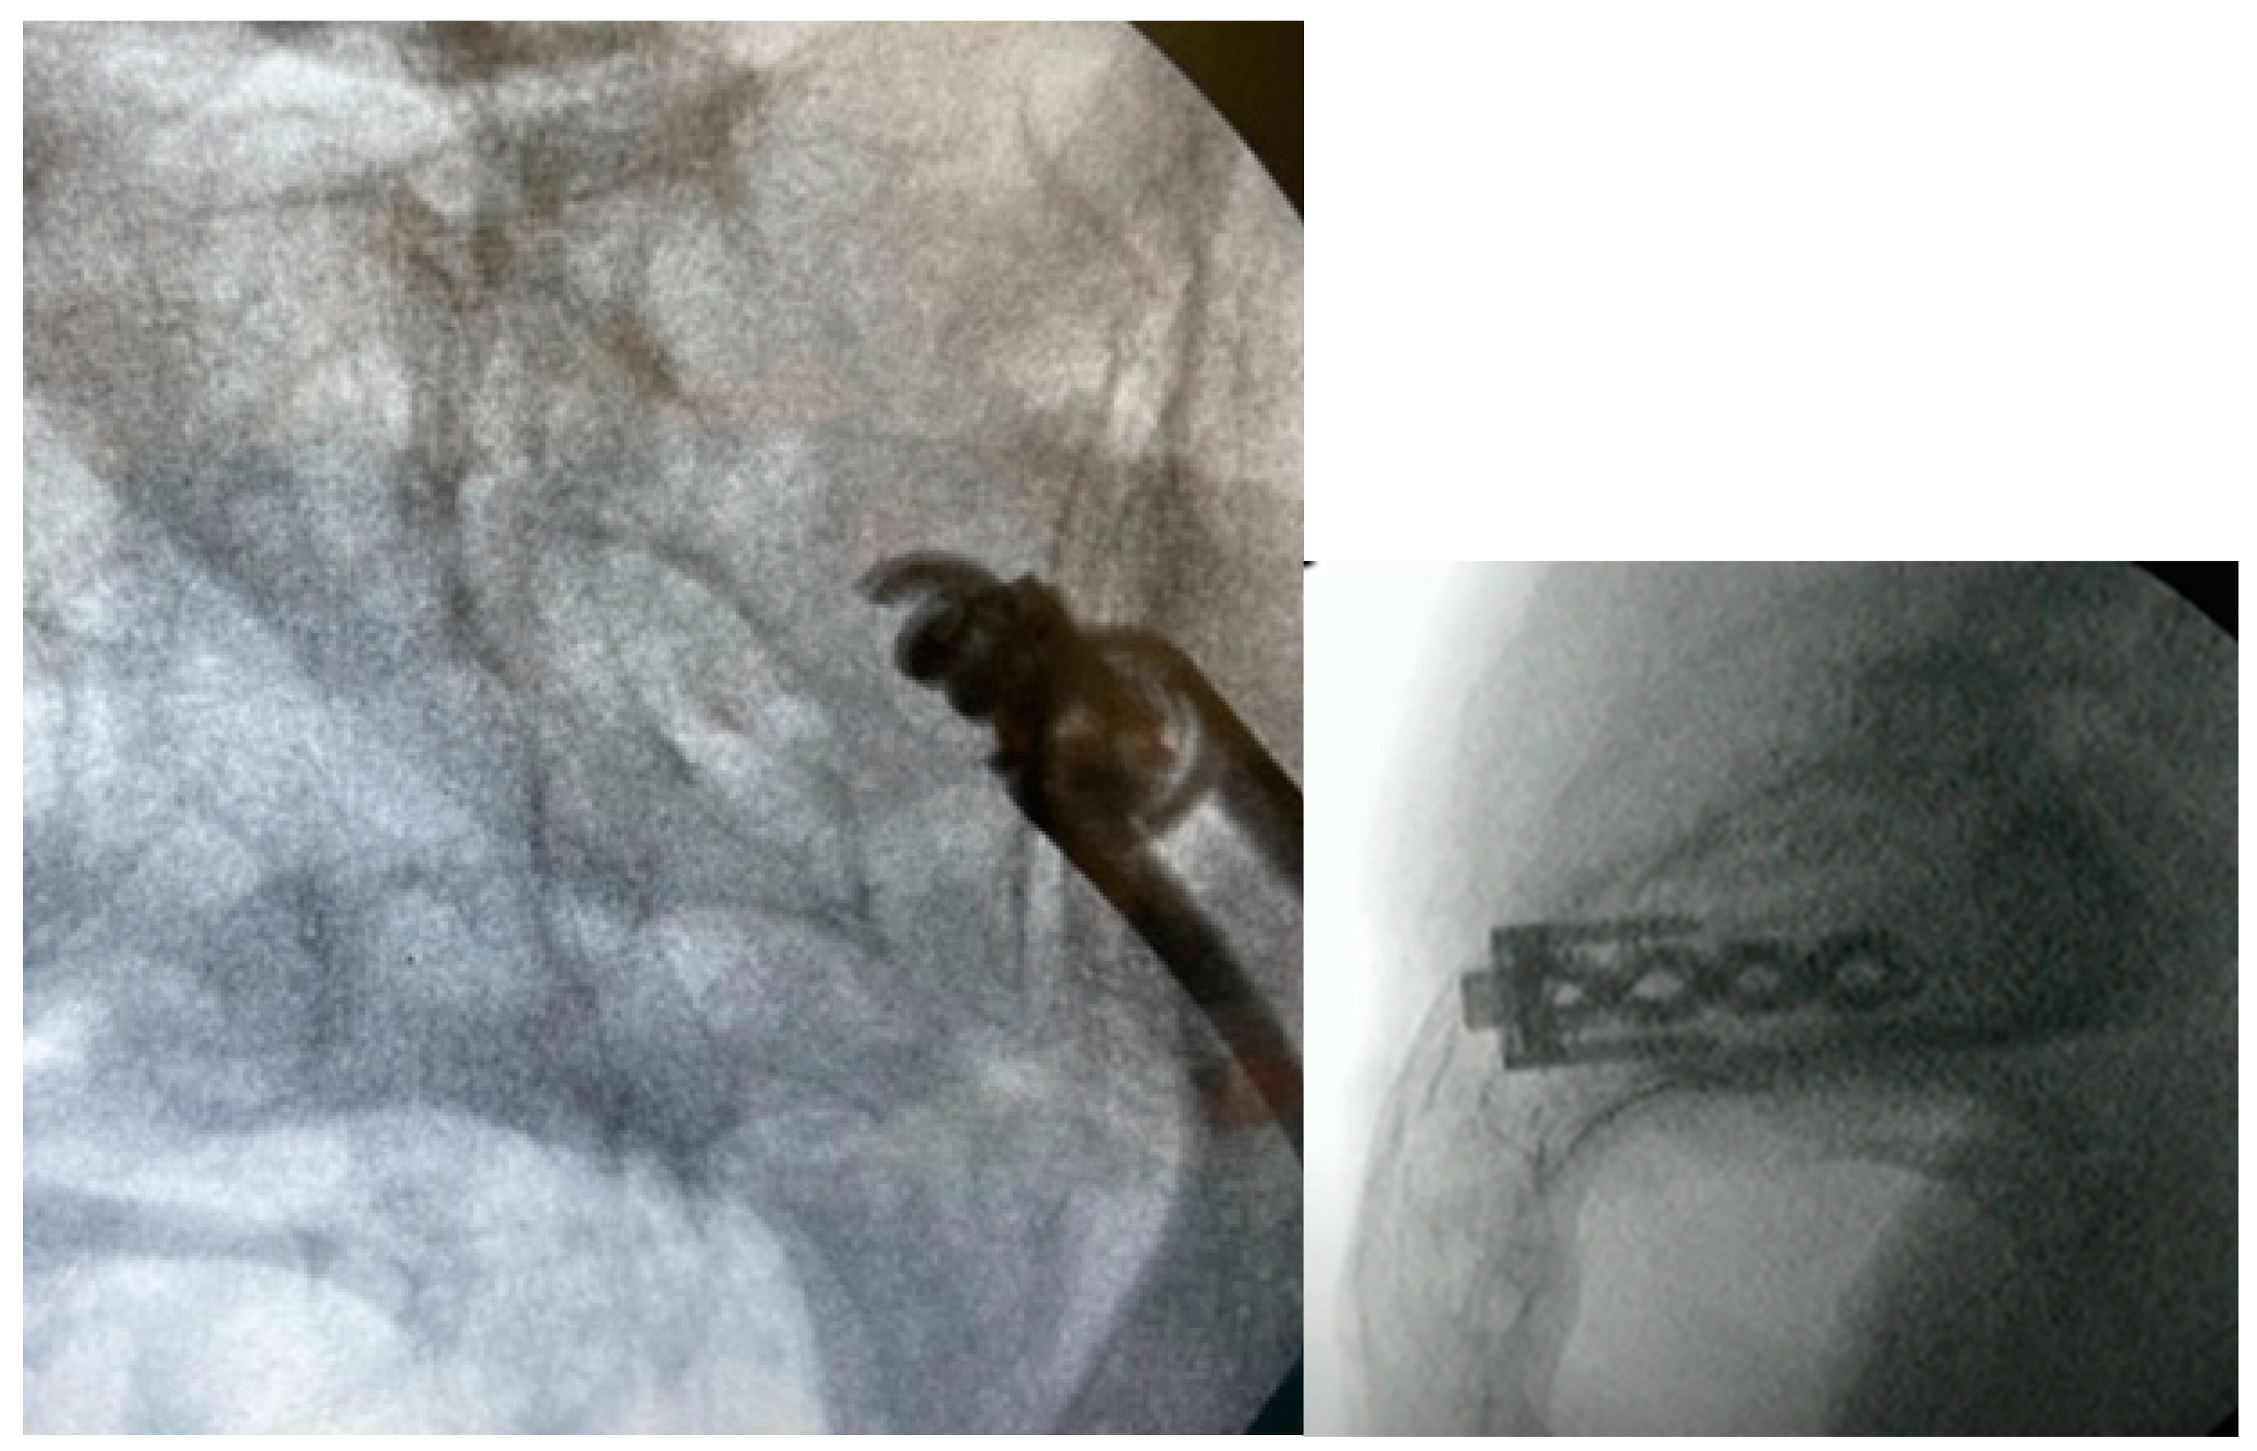

3.3.7. Docking Washer Introduction

3.3.8. Implant Insertion